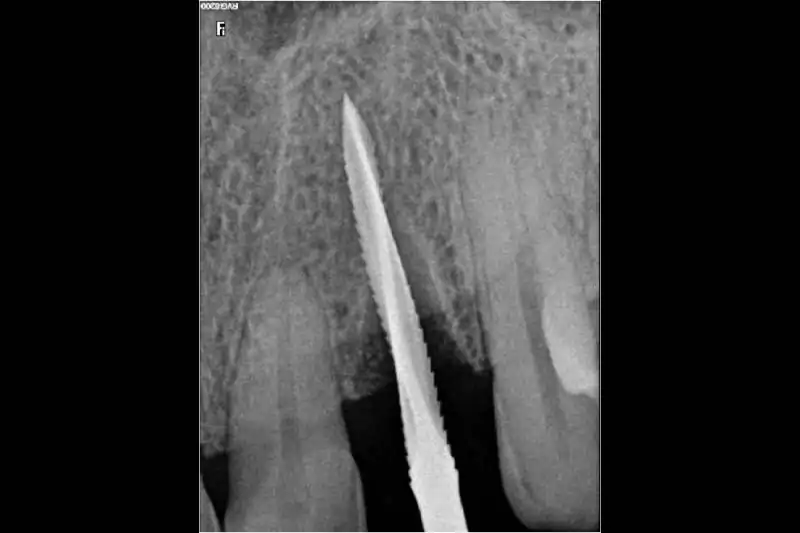

Smilex Advanced Dental Care proudly offers world-class Same Day Dental Implants Treatment in India, enabling you to regain full dental function in just one visit. Whether you've lost a single tooth or multiple, our expert implantologists use advanced digital scans, CBCT imaging, and CAD/CAM-supported restorations to provide precise, long-lasting results.

Same Day Implantology is an advanced dental procedure that allows for the replacement of missing teeth with dental implants in just a single appointment. Unlike traditional methods that involve multiple visits and a lengthy healing period, Same Day Dental Implants In India offer a more efficient and convenient solution, providing immediate results. This process involves precise digital planning to ensure the correct placement of implants, improving both the speed and success rate of the procedure. Additionally, if you’re considering a complete smile transformation, understanding the Full Mouth Dental Implant Cost In India will help you make an informed decision about this quick and effective treatment option. With modern technology and expert care, you can restore your smile in no time while maintaining long-term oral health.

Teeth extraction (if necessary) and implant placement.Temporary crowns or bridges attached for immediate function and aesthetics.